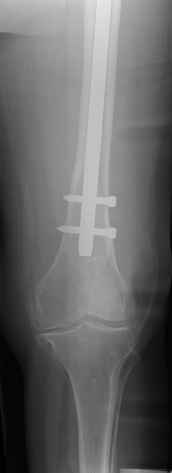

4. We could treat this fracture like there is no a nail - new locking plates allow for secure fixation.... two similar cases are attached...

Images sent by Professor Kanlic look nice, very good job. Excellent achorage in distal fragment. However, unicortical screwing or bicortical

makes a difference, also for locked screws. Proximal fragment unicortical fixation may present stability not easlily predictable. Certainly its stability for wheelchair should be sufficient. Full weight bearing can not be mentioned for this case. If minimal bearing is allowed full weight

single step may happen in elderly.

Gamma nail exchange may probably fit the criteria of optimal and minimal invasivness, indeed. Removal could be relatively fast due to large intramedullary diameter seen on X-ray.

I do agree that distal locking of the nail in distal femur remains critical.

Images sent by Professor Kanlic look nice, very good job. Excellent achorage in distal fragment. However, unicortical screwing or bicortical makes a difference, also for locked screws. Proximal fragment unicortical fixation may present stability not easlily predictable. Certainly its

stability for wheelchair should be sufficient. Full weight bearing can not be mentioned for this case. If minimal bearing is allowed full weight

Gamma nail exchange may probably fit the criteria of optimal and minimal invasivness, indeed. Removal could be relatively fast due to large

intramedullary diameter seen on X-ray.

Good day dears colleguaes! In this case I'd like to use distal femoral lock plate with locking across nail through two holes of nail and number monocortical screws on proximal fragment. This technique demand some skill but be posible.